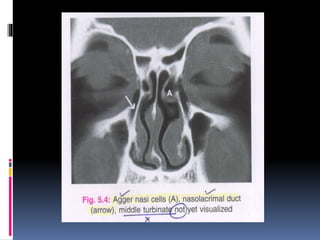

 Agger nasi: This is a bony prominence that is often

pneumatized in the ascending process of the maxilla. Its

location below the frontal sinus also defines the anterior

limit of the frontal recess